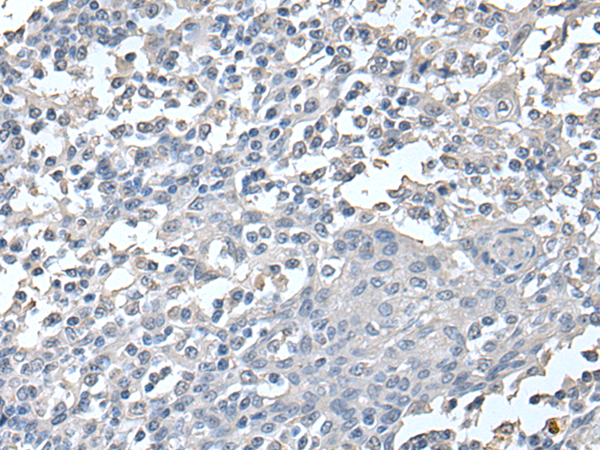

分类: 科研抗体货号: P12751别名: OMI; MGCA8; PARK13; PRSS25应用: WB,IHC反应种属: Human, Mouse